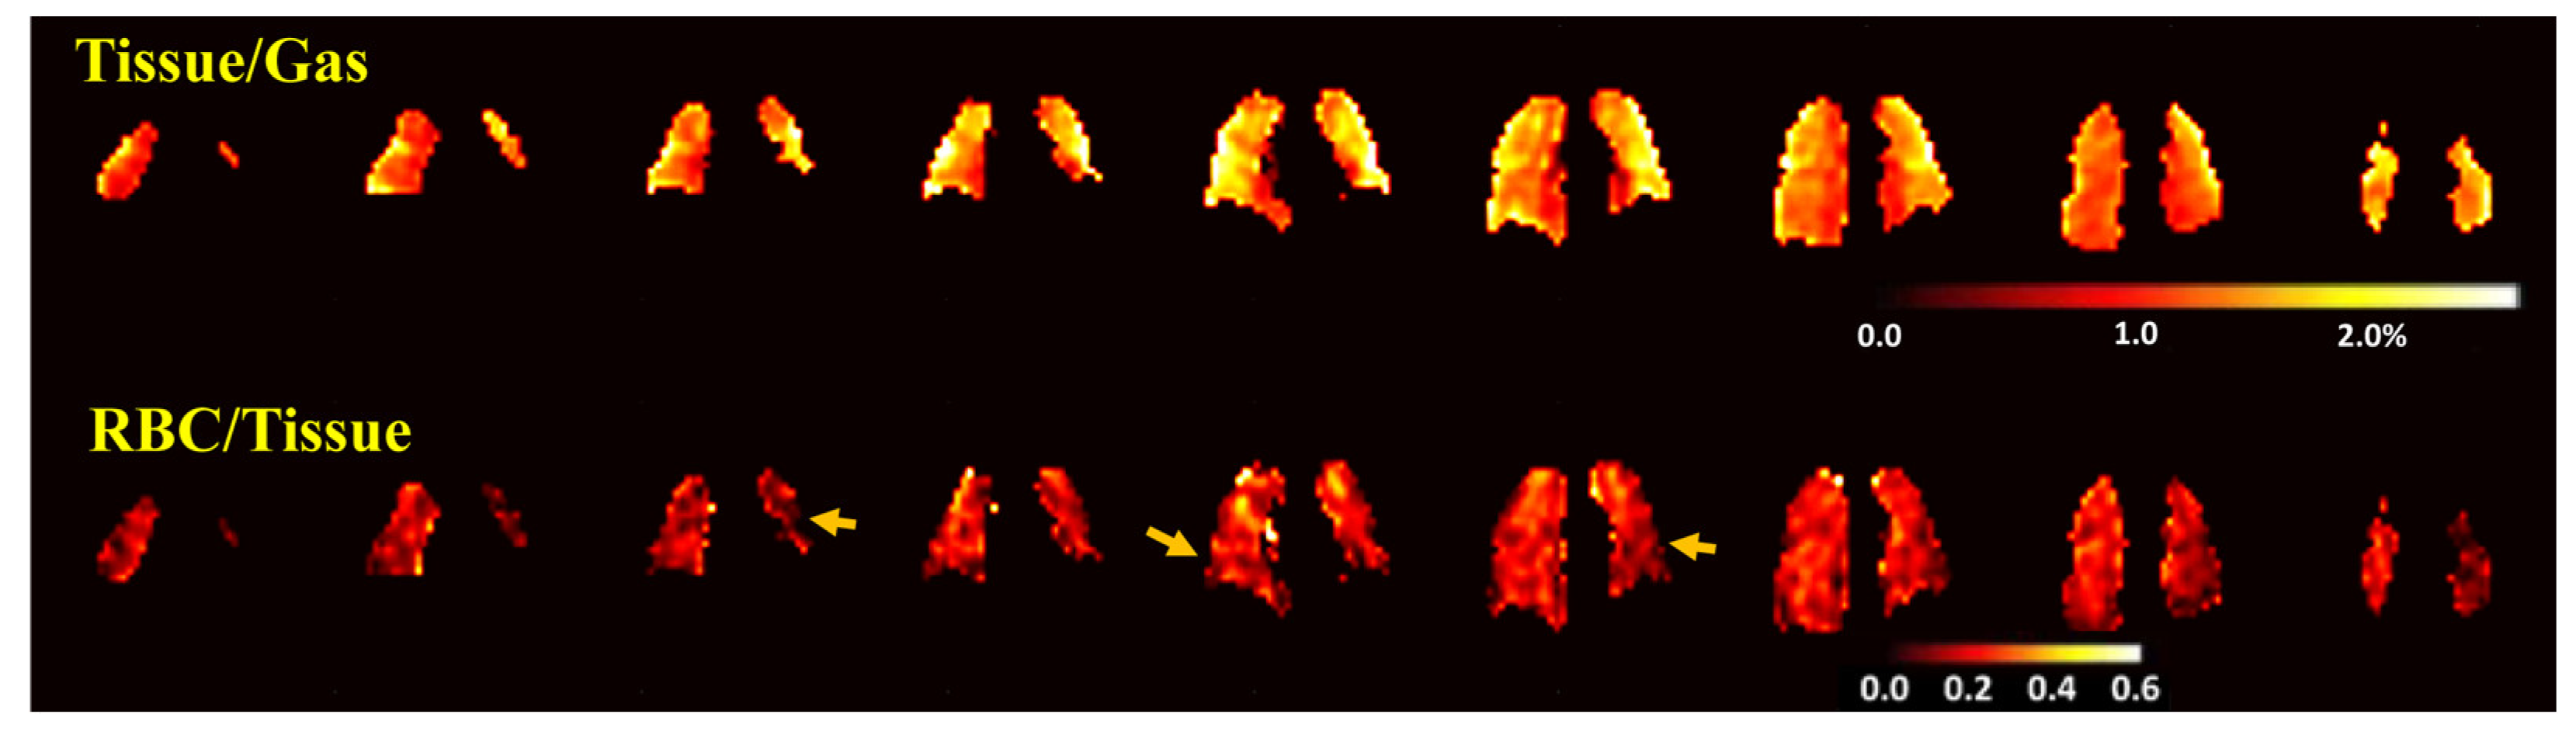

3.3. Measures from Dissolved-Phase 129Xe MRI and Comparison with CT

| Tissue-to-gas ratio | 1.0 (0.97–1.2) | 1.4 (1.3–1.6) | 0.014 | |

| RBC-to-tissue ratio | 0.27 (0.22–0.28) | 0.20 (0.18–0.23) | 0.004 |